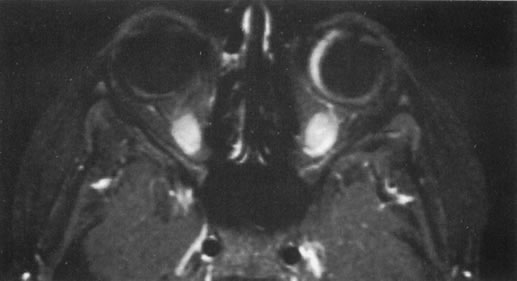

Ocular involvement is a common presentation of acute myelomonocytic leukemia in children from the Mediterranean area.57 These children often present with simultaneous ocular and orbital tumor.58,59 In a few cases, we have established the correct diagnosis with an anterior chamber paracentesis. Most American children managed for leukemia-associated ocular problems, however, have the acute form of lymphocytic disease, and ocular problems usually develop as a sign of systemic or CNS relapse. In rare cases, an anterior chamber collection of malignant cells (similar in appearance to Fig. 21) or tumor infiltrating the optic nerve head can be the presenting sign of this disease.58,59 Rarely, where the possibility of intraocular recurrence of acute lymphocytic leukemia is not recognized and topical corticosteroids are given for presumed anterior uveitis, the anterior chamber clears and the patient presents with a ciliary body mass (Fig. 27).

Fig. 27. A patient who had an ocular relapse of acute lymphocytic leukemia treated with topical corticosteroids because the symptoms were presumed to be due to anterior uveitis. As a result, the anterior chamber cleared and the patient presented with a ciliary body mass. The magnetic resonance image demonstrates a pseudoscleritis in that eye.